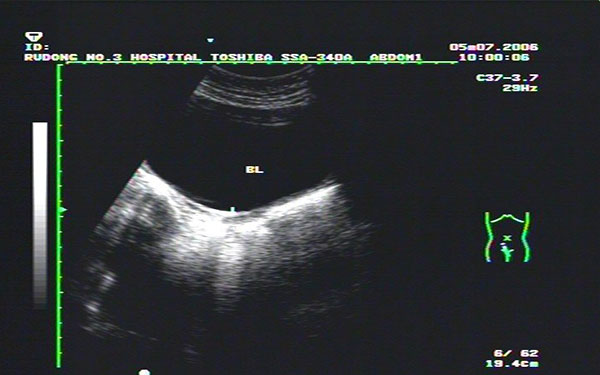

始基子宫的诊断可依靠电子阴道镜,腔内四维彩超,染色体分析和电化学发光法内分泌检测就可确诊。其超声诊断表现为: